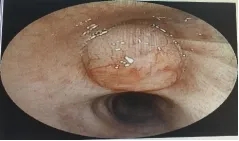

入院第2天完善支气管镜检查,如下图:

镜下图像:右上叶开口可见带蒂团状光滑肿块